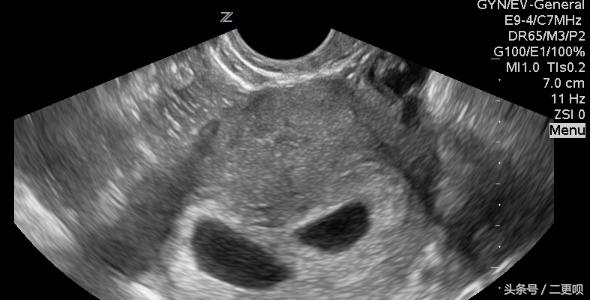

• 附上当时孕7周的B超单

孕7周B超单

附上孕12周+3B超时的照片

孕12周B超图